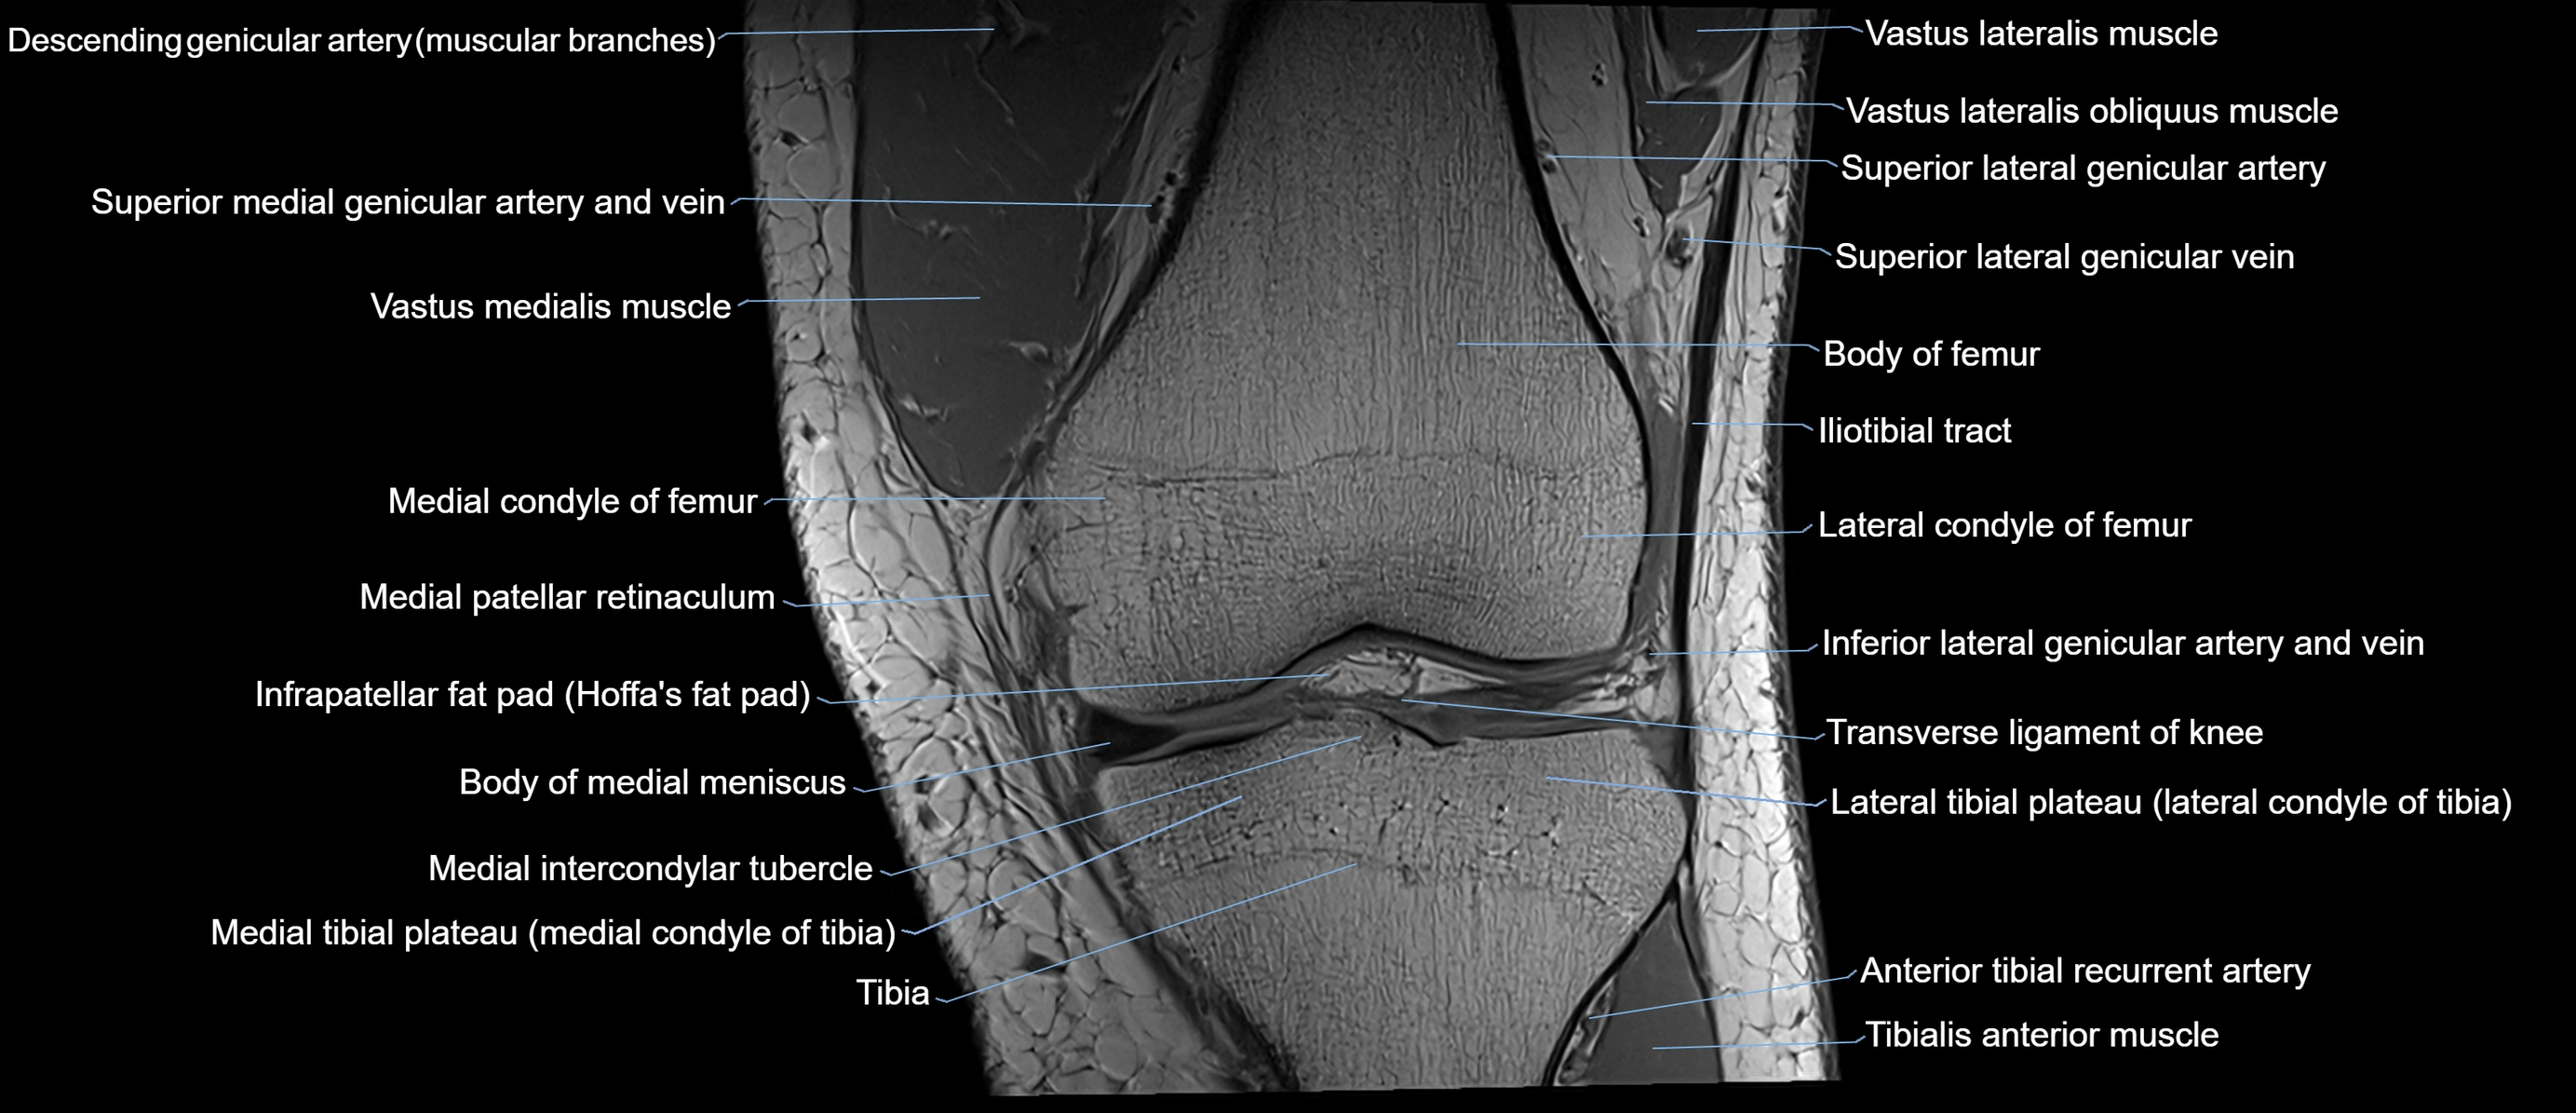

- Body of medial meniscus

- Medial condyle of femur

- Medial condyle of tibia

- Medial intercondylar tubercle

- Medial patellar retinaculum

- Medial tibial plateau

- Tibia

- Tibialis anterior muscle

- Transverse ligament of knee

- Vastus lateralis muscle

- Vastus medialis muscle